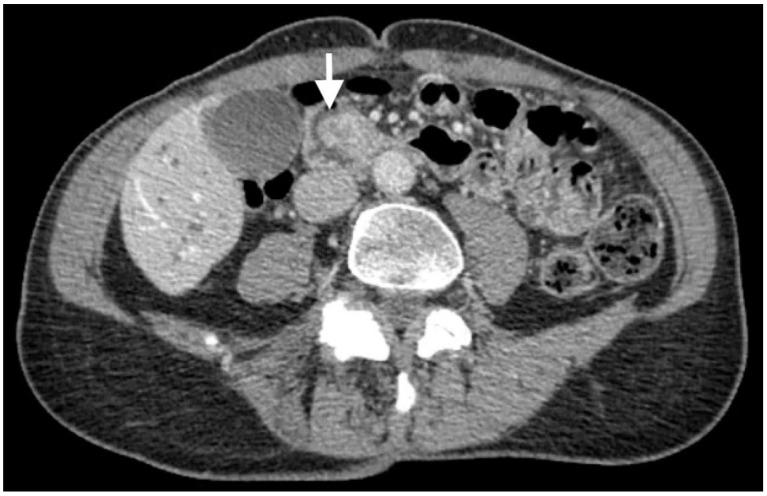

Ampullary adenocarcinoma is a rare malignancy that lacks standard systemic treatment. We describe a case of recurrent metastatic ampullary adenocarcinoma of the pancreaticobiliary subtype treated with nanoparticle albumin-bound (nab)-paclitaxel and gemcitabine as first-line treatment. This report also highlights the molecular profile of the ampullary adenocarcinoma and circulating tumor DNA (ctDNA). This is a case of pancreaticobiliary ampullary adenocarcinoma in a 67-year-old woman who initially presented with painless jaundice. Endoscopic and imaging evaluation revealed biliary ductal dilation secondary to an ampullary mass. Pathology confirmed the diagnosis of ampullary adenocarcinoma of the pancreaticobiliary subtype. She underwent surgical resection of the tumor, followed by adjuvant chemotherapy with gemcitabine and capecitabine. The tumor subsequently recurred in the liver. She received palliative chemotherapy with nab-paclitaxel and gemcitabine, resulting in an objective tumor response for 14 months. Molecular profiling of the tumor and ctDNA revealed a novel RNA fusion and a novel mutation, respectively. Our report suggests that long-term durable response can be achieved in metastatic pancreaticobiliary ampullary adenocarcinoma using nab-paclitaxel and gemcitabine. Molecular profiling of the tumor identified a novel RNA fusion and mutation that can be potentially targeted for treatment.

壶腹腺癌是一种罕见的恶性肿瘤,缺乏标准的全身治疗方法。我们描述了一例复发性转移性胰胆管亚型壶腹腺癌,该患者一线治疗采用纳米白蛋白结合型(nab)紫杉醇和吉西他滨。本报告还重点介绍了壶腹腺癌的分子特征和循环肿瘤DNA(ctDNA)。这是一名67岁女性的胰胆管壶腹腺癌病例,最初表现为无痛性黄疸。内镜和影像学评估显示,壶腹肿块继发胆管扩张。病理确诊为胰胆管亚型壶腹腺癌。她接受了肿瘤手术切除,随后接受了吉西他滨和卡培他滨辅助化疗。肿瘤随后在肝脏复发。她接受了nab紫杉醇和吉西他滨姑息化疗,肿瘤客观缓解达14个月。肿瘤和ctDNA的分子分析分别发现了一种新的RNA融合和一种新的突变。我们的报告表明,使用nab紫杉醇和吉西他滨可使转移性胰胆管壶腹腺癌获得长期持久缓解。肿瘤的分子分析确定了一种新的RNA融合和一种可潜在用于治疗靶点的突变。